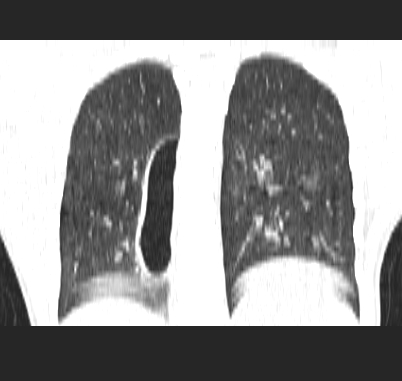

标题: CT19170:男 24岁,胸部外伤一周行CT检查 [打印本页]

男 24岁,胸部外伤一周行ct检查 未传纵隔窗

结合病史考虑肺挫伤后所致的肺气囊表现

结合临床考虑为右肺下叶背段撕裂伤。

首先考虑肺裂伤形成的液气囊肿.纵膈胸膜包裹性的液气胸可能性小,病变主要在肺内.

支持外伤性肺气囊。

肺撕裂伤液气囊形成

考虑外伤肺撕裂致右肺下叶纵隔胸膜下液气囊肿。

结合临床考虑为右肺下叶背段撕裂伤后形成局限性包裹性的液气胸。